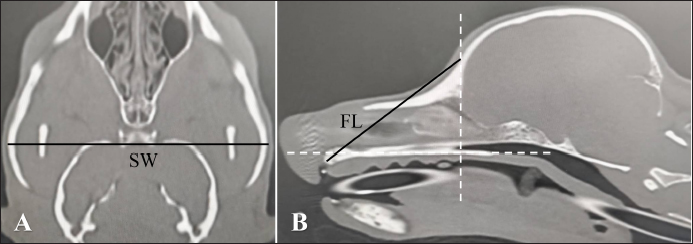

Nasal septum deviation is one of the normal anatomical individual differences (Miles and Schwarz, 2020). The air percentage and contrast enhancement of nasal mucosa in the right and left nasal cavities can change when the nasal septum deviation concentrates nasal structures either on the right or left nasal cavity. In other words, it is difficult to determine whether the changes in patients with nasal septum deviation are caused by nasal inflammation or simple individual differences. Therefore, this study examined the right–left ratio of the air percentage and contrast enhancement in normal dogs with remarkable nasal septum deviation. Chihuahuas and Shih tzus were considered because nasal septum deviation can be easily found in these breeds compared with Miniature dachshunds, Toy poodles, and Shibas. However, since there are no distinct criteria regarding the presence and degree of nasal septum deviation, a standard indicating that “nasal septum deviation is remarkable” was needed in Chihuahuas and Shih tzus. Thus, after measuring the angle of nasal septum deviation in both breeds, dogs whose minor angle sides of nasal septum deviation were median value or less were selected. Based on previous studies (Auger et al., 2016; Miles and Schwarz, 2020), the degree of nasal septum deviation was defined as APB, where (A) is the dorsal point of the nasal septum; (P) is the most deviated point of the nasal septum; and (B) is the ventral point of the nasal septum, which is the binding site of the nasal septum and vomer (Fig. 1). Regarding each dog, transverse sections on which the degree of nasal septum deviation was visually the largest were selected for APB measurement. The CT images reconstructed with bone function were used for measuring APB. The window configurations were as follows: window width 1,500 and window level −300. After measurement, the air percentage was analyzed in eight Chihuahuas and eight Shih tzus whose APB values were median values or less. Since the direction of nasal septum deviation was not always similar, the right and left nasal areas were defined as the major and minor angle sides. After calculating the air percentage on the major and minor angle sides using the method mentioned above, the proportion of the air percentage on the minor angle side to that on the major angle side was calculated. In addition, differences in contrast enhancement were analyzed. However, the post-contrast CT images were not obtained in three Chihuahuas. Therefore, the CT images of six Chihuahuas and eight Shih tzus whose APB values were median value or less were selected. After calculating the contrast enhancement on the major and minor angle sides using the method mentioned above, the proportion of contrast enhancement on the minor angle side to that on the major angle side was calculated.

Fig. 1. CT measurements for ∠APB at the maximum level of nasal septum deviation (axial section). A: the dorsal, B: the ventral, and P: the most deviated point of the nasal septum window width: 1,500, window level: −300.